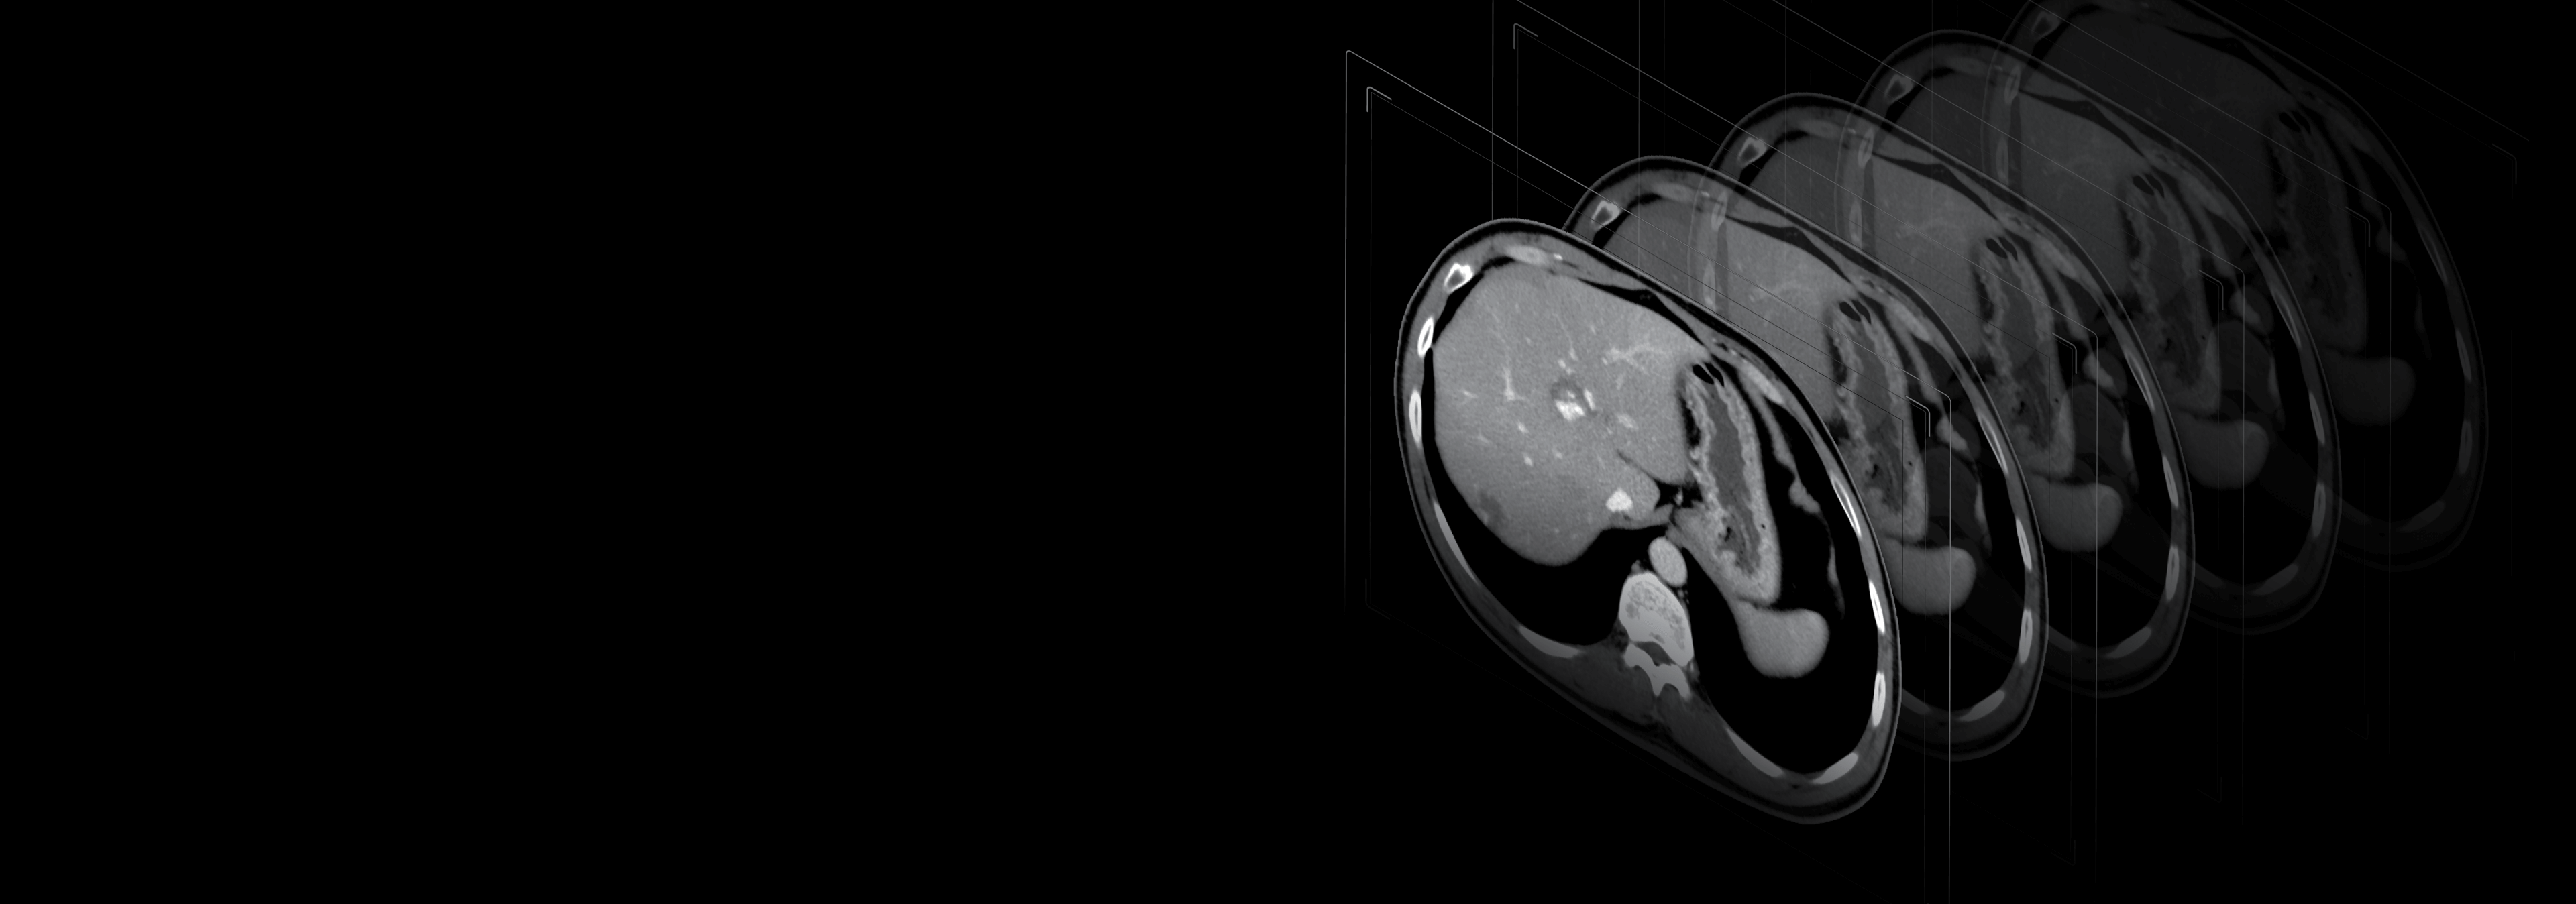

70kV扫描模式

大幅降低辐射剂量,提高造影剂对比度,使微小病变等临床应用难点被突破